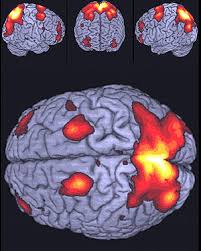

El estudio identifica cómo esta relación funciona en el cerebro. Esto demuestra que las personas con mayor sensibilidad a la recompensa muestran una mayor actividad en cinco áreas clave del cerebro implicadas en la motivación o recompensa, y que este aumento ocurre cuando simplemente miran las fotos de platos de comida. Los científicos, dirigidos por John Beaver, utilizaron tecnología para escaneo cerebral conocida como resonancia magnética funcional.

El estudio encontró que, cuando se les mostraron fotos de comida apetitosa, las personas con sensibilidad a la recompensa más alta, tenían hasta el doble del nivel de actividad en las cinco áreas del cerebro implicadas con la recompensa - conocida como la red neuronal - en comparación con aquellos con menor sensibilidad a la recompensa.